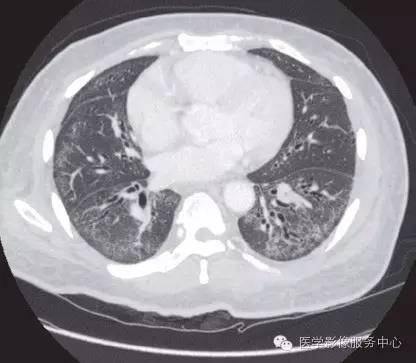

采取的治疗包括高剂量泼尼松、 静脉注射免疫球蛋白和青霉胺。尽管如此患者钙化依然在进展,逐渐导致手指、 手、 脚趾、 右胸和右大腿的功能障碍。外科松解手术虽可暂时缓解疼痛,但是不能控制钙化的进展。查体可见累及手掌以及所有手指未愈合溃疡的广泛软组织钙化,并伴有屈曲畸形。同样的广泛钙化也在X线片和胸部CT检查中被发现。

系统性硬化是一种以独特的病理三联征为主要表现的自身免疫性疾病,即微血管损害、固有免疫和适应性免疫功能失调以及多种器官纤维化。尽管皮肤纤维化是其最特征性的表现,但肺部、胃肠道、肾脏以及心脏的病理改变是临床预后的决定性因素。系统性硬化患者具有很明显的异质性,包括临床表现、自身抗体、疾病进展、治疗反应以及生存率等

系统性硬化相关性间质性肺疾病的早期表现